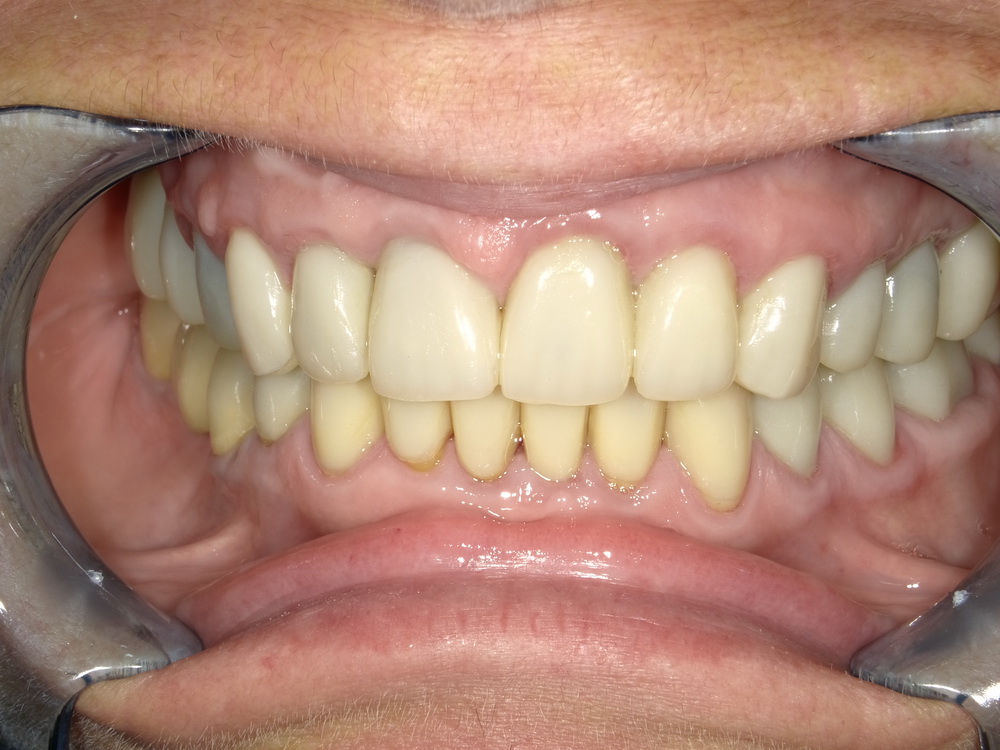

Nach mehreren Monaten Erprobungszeit der funktionstherapeutisch eingestellten Bisslage beginn nunmehr die Umsetzung der Versorgung mit Laborgfertigten Dauerprovisorien in eine Versorgung mit definitiven zahntechnischen Kronen.

Die neue Versorgung beginnt mit der Entfernung der Dauerprovisorien im Unterkieferseitenzahnbereich.